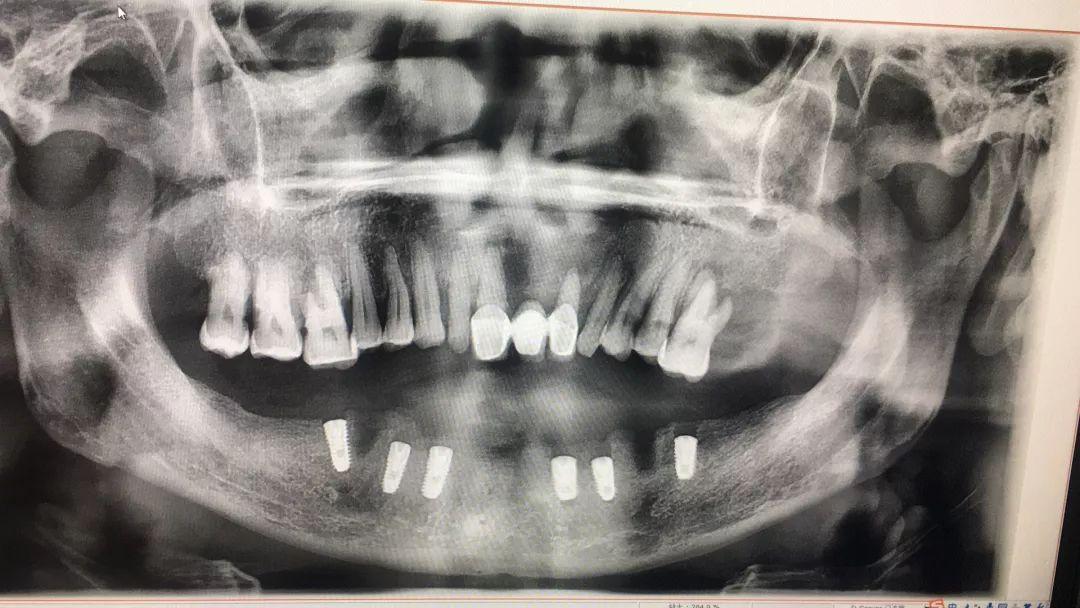

在7月18日上午,由廣大口腔的王利暉主任為何叔做了下半口的種植手術(shù),拔除松動(dòng)牙齒后植入6顆種植體。術(shù)前何叔對(duì)工作人員說:“先種下半口的,上半口遲些再種。要是果好,我還是認(rèn)定廣東省愛牙工程和廣大口腔。